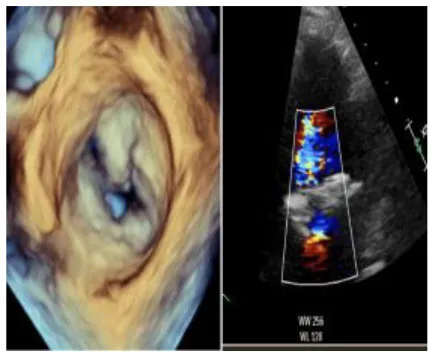

The usual intraoperative strategy continues with median sternotomy, inverted T-opening of the pericardium, and placement of suspension stay-sutures, followed by bicaval cannulation. Once established, the extracorporeal circulation and the venae cavae are both tightened, and the aorta clamped. Del Nido anterograde cardioplegia is administered. With the heart under cardioplegic arrest, the left atrium is linearly incised along Waterston's groove for optimal exposure of the MV. Our policy is to avoid massive debulking in patients with severe calcifications, removing only the anterior mitral leaflet so that the valve can be measured and then replaced. This step is very delicate and must be precise so as not to obstruct the LVOT. It is advisable to flush regularly with a hydro-saline solution to remove any residual calcium. At this time, the size of the Sapien 3 Ultra prosthesis (Edwards Lifesciences, CA, USA) can be measured and confirmed. The pericardial skirt can be sutured on the atrial side (4–0 polypropylene monofilament thread; Figure 1). Here, the recommendation is to have great meticulousness when suturing the Sapien pericardial skirt: it is very easy to have small folds in the sutured pericardium, which becomes moderate leaks under pressure once the circulation has been restarted. Once the valve is ready, it is crimped together with the skirt on a short delivery system (for transapical access TAVI), taking care not to ruin it (Figure 2). To have the correct coaxiality between the MV and the left ventricle, the nose cone was almost completely flexed toward the mitral apex so that the insertion under direct vision becomes physiological. Once accomplished, the pericardium is fixed with other annular pledgeted sutures previously placed through extensive calcifications. The valve is further fixed to the ring with two or four Ethibond 2–0 cardinal stitches (Figure 3).

Figure 3

Three panels of figures (A–C) depicting the intraoperative placement of pericardial skirt stitches [radial as for a replacement (A) the implant (B) and the final result (C)].